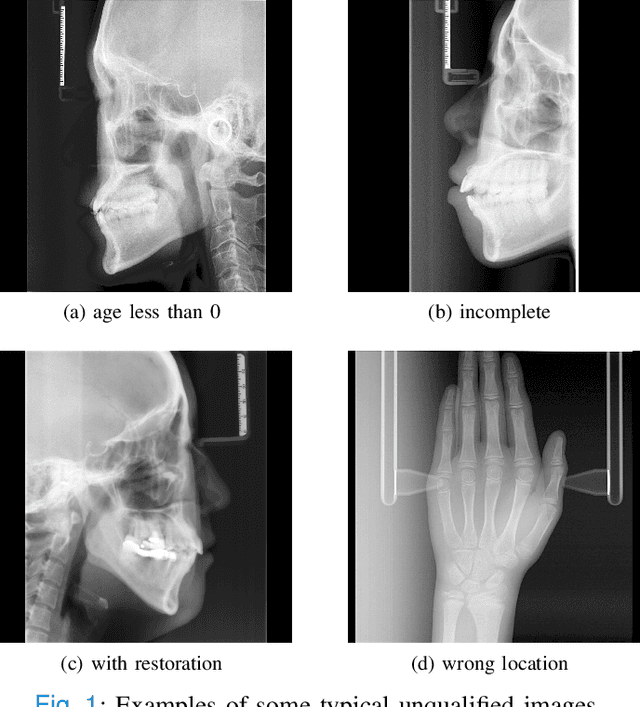

The traditional manual age estimation method is crucial labor based on many kinds of the X-Ray image. Some current studies have shown that lateral cephalometric(LC) images can be used to estimate age. However, these methods are based on manually measuring some image features and making age estimates based on experience or scoring. Therefore, these methods are time-consuming and labor-intensive, and the effect will be affected by subjective opinions. In this work, we propose a saliency map-enhanced age estimation method, which can automatically perform age estimation based on LC images. Meanwhile, it can also show the importance of each region in the image for age estimation, which undoubtedly increases the method's Interpretability. Our method was tested on 3014 LC images from 4 to 40 years old. The MEA of the experimental result is 1.250, which is less than the result of the state-of-the-art benchmark because it performs significantly better in the age group with fewer data. Besides, our model is trained in each area with a high contribution to age estimation in LC images, so the effect of these different areas on the age estimation task was verified. Consequently, we conclude that the proposed saliency map enhancements chronological age estimation method of lateral cephalometric radiographs can work well in chronological age estimation task, especially when the amount of data is small. Besides, compared with traditional deep learning, our method is also interpretable.